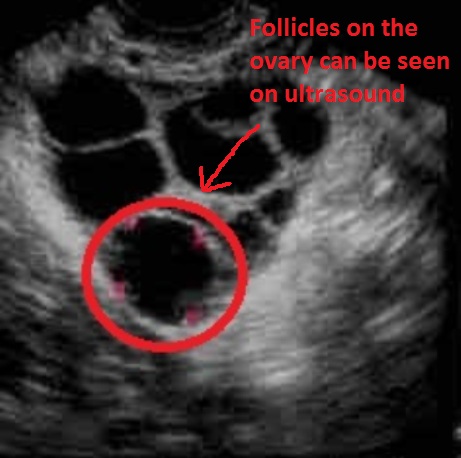

Спкя На Узи Фото

Спкя На Узи Фото 113 фотографий